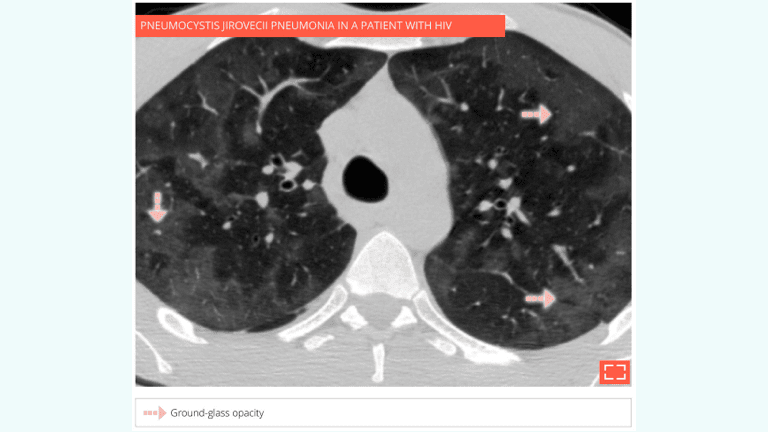

• Ground-glass opacity can be associated with various conditions:

• Pulmonary oedema

• Pulmonary infection: pneumocystis jirovecii pneumonia, cytomegalovirus (CMV), etc.